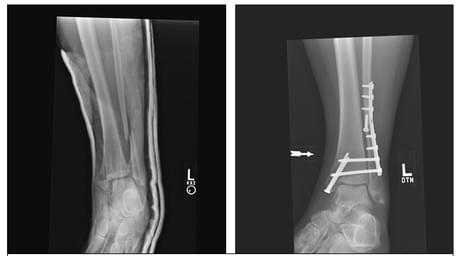

Клинический случай 2. Перелом обеих лодыжек с вывихом стопы кнаружи, кзади.

44 А3-3

Пациентка Л. 50 лет, травма в быту, получила закрытый перелом обеих лодыжек с вывихом стопы кнаружи и кзади. Данный случай интересен значительным повреждением мягких тканей произошедшем при травме и потребовавшем значительных усилий в борьбе с отёком, а также морфологией перелома внутренней лодыжки, сломавшейся одним большим блоком вместе с задним краев большеберцовой кости, что потребовало её фиксации при помощи пластины и винтов.

В связи с выраженным отёком мягких тканей, высоким риском некроза краёв ран и инфекционных осложнений пациентке с целью предоперационной подготовки выполнялись скелетное вытяжение, сосудистая и метаболическая терапия, лимфодренаж, физиотерапия. После спадения отёка, на 3 день после поступления выполнено оперативное вмешательство: открытая репозиция, остеосинтез переломов наружной и внутренней лодыжек пластинами и винтами.

Через 4 дня пациентка выписана на амбулаторное долечивание. Послеоперационные раны зажили первичным натяжением, швы удалены через 14 дней.

Через 6 недель после первичного вмешательства произведено удаление позиционного винта, пациентка приступила к активной разработке движений в голеностопном суставе.

Амплитуда движений через 8 недель после травмы и оперативного вмешательства по поводу этого тяжёлого повреждения близка к полной. Пациентка ходит с полной опорой, не используя костыли или трость, не хромает, боли не беспокоят. Сохраняется умеренный отёк в области голеностопного сустава.